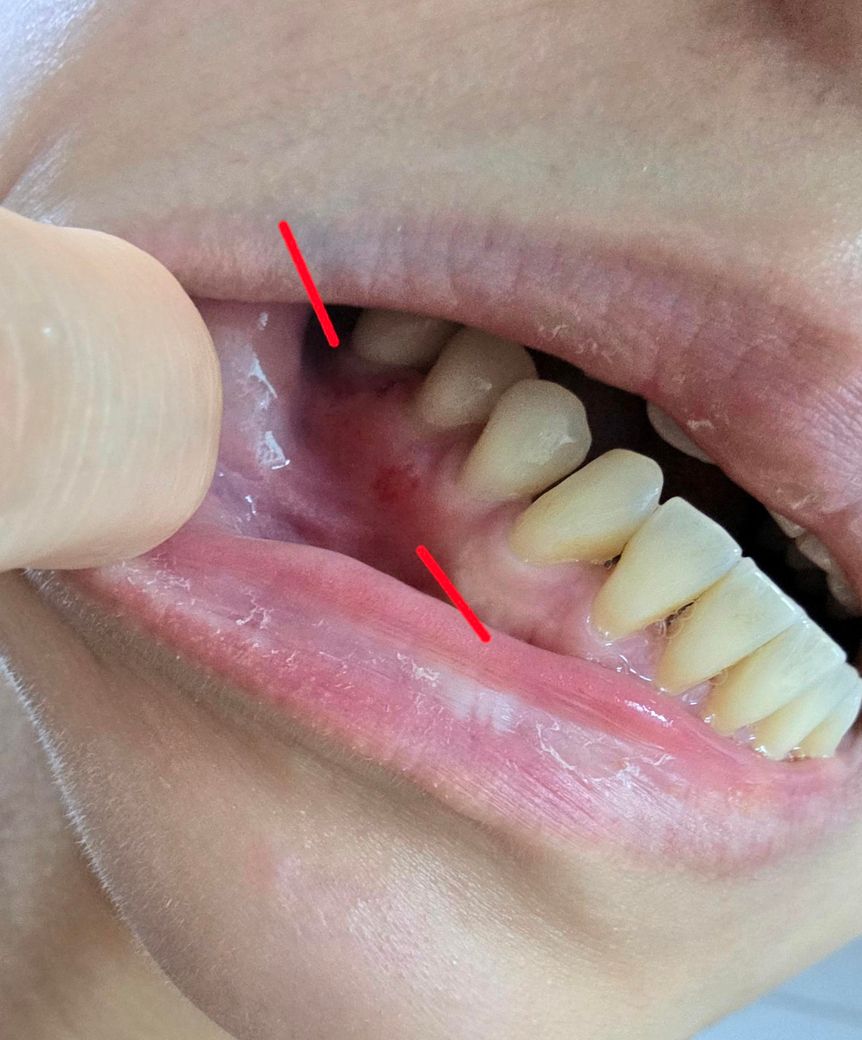

안녕하세요. 수요일에 스케일링후 치아뿌리쪽이 깨졌다며 레진을 하여야한다고 하여 레진을 진행하였는데요.

진료직후부터 불편감이 있었는데.

오늘 보니 레진한 치아잇몸쪽으로 붓기와 주변이 빨갛게 되어있습니다ㅠㅠ

(사진상으로 잘안보이는데. 붓진 않았지만

빨간점 찍힌 치아주변으로 빨갛고 빨간반점들도 보여요)

빨간점 찍혀있는 치아 뿌리아래쪽 레진했다고

하였는데.

사진으로 봤을 경우에는 치아 사이에 염증이 있는 것으로 보입니다. 염증의 원인이 치아에서 유발된 것이라면 신경치료 등이 필요할 수 있습니다. 단순히 잇몸에 손상이 가해져서 생긴 염증이라면 이수정도 지나면 대부분 없어지게 됩니다.

잇몸에 농양이 생긴 것 같은데 꼭 스케일링이나 레진 때문은 아닐 것 같고 치과가서 엑스레이 찍어보고 검사해봐야할 것 같습니다